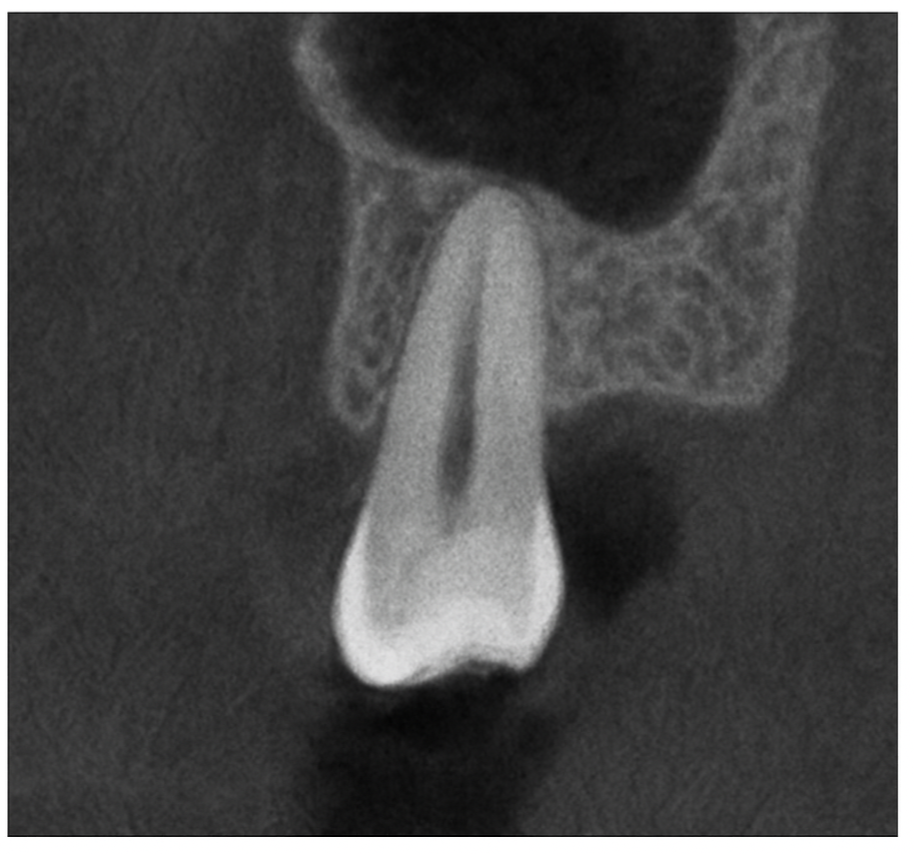

The Panoramic OP 3D LX is an advanced dental imaging system designed to provide a complete, high-resolution view of your entire mouth in a single image. This technology captures your teeth, jawbones, and surrounding structures with remarkable clarity, helping dentists identify issues such as cavities, infections, bone loss, and impacted teeth. Its quick, comfortable process makes it an excellent tool for routine check-ups, pre-treatment evaluations, and surgical planning. The OP 3D LX minimizes patient radiation exposure while maximizing diagnostic accuracy, ensuring a safe and effective experience for every patient.